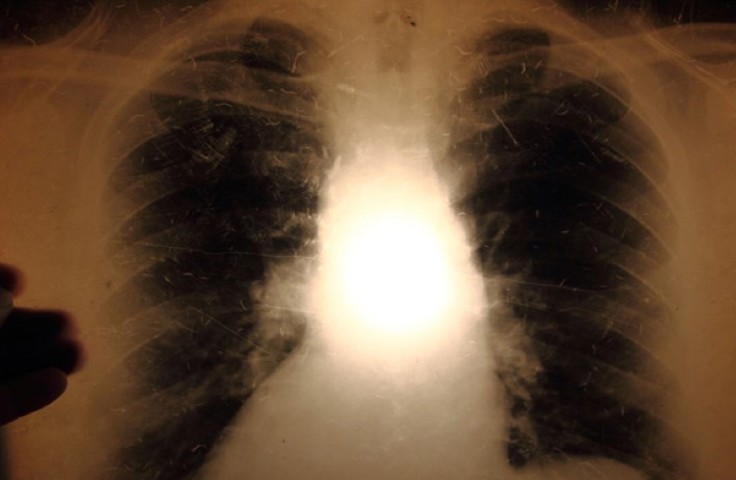

Examination for tuberculosis disease: If the screening for tuberculosis infection is positive, an X-ray examination of the lungs will be performed to detect any tuberculosis disease. A chest X-ray can also be used as a first examination if tuberculosis is suspected, or as part of a screening.